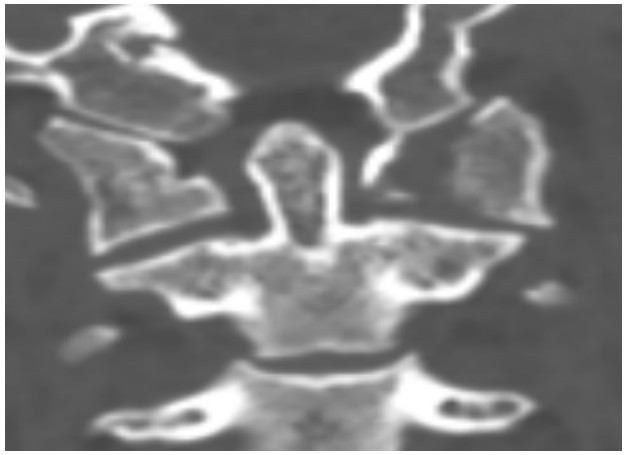

國慶節(jié)前一天,譚女士不幸被門框砸傷頸部,劇烈的疼痛和頸椎的活動受限讓她的世界瞬間陷入了黑暗。在經(jīng)歷了初步的檢查后,譚女士被診斷為寰椎骨折,這個診斷如同一道晴天霹靂,讓她和家人的心沉入了谷底。絕望中,譚女士被緊急轉(zhuǎn)至衡陽市中心醫(yī)院骨科一區(qū)(脊柱外科),錢軍博士及其團(tuán)隊(duì)在接到這一緊急病例后迅速接診,經(jīng)過細(xì)致的病史詢問、體格檢查和影像學(xué)資料分析,確診譚女士的寰椎骨折伴有寰樞椎體不穩(wěn)定,迫切需要手術(shù)治療以恢復(fù)其穩(wěn)定性。考慮到上頸椎手術(shù)的高風(fēng)險性,特別是寰樞椎周圍結(jié)構(gòu)復(fù)雜,緊鄰椎動脈和脊髓,手術(shù)過程中的任何微小失誤都可能導(dǎo)致災(zāi)難性后果,錢軍博士團(tuán)隊(duì)頂著壓力,迎難而上,沒有絲毫猶豫,立即行急診手術(shù),投入到緊張的救治工作中。